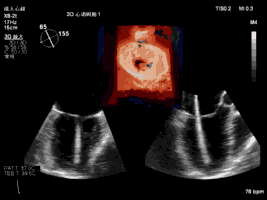

本例手术使用TrueVue实时三维双容积视野同时显示二尖瓣左房观和左室观,画面清晰,界面友好,使得手术操作“如虎添翼”,更加便捷和安全。本例手术导管操作总时间(从穿刺心尖到闭合心尖)仅为10分钟。系列图像如下:

夹合术中:三维心超示输送鞘跨瓣

夹合术中:三维心超示夹合器捕获瓣叶